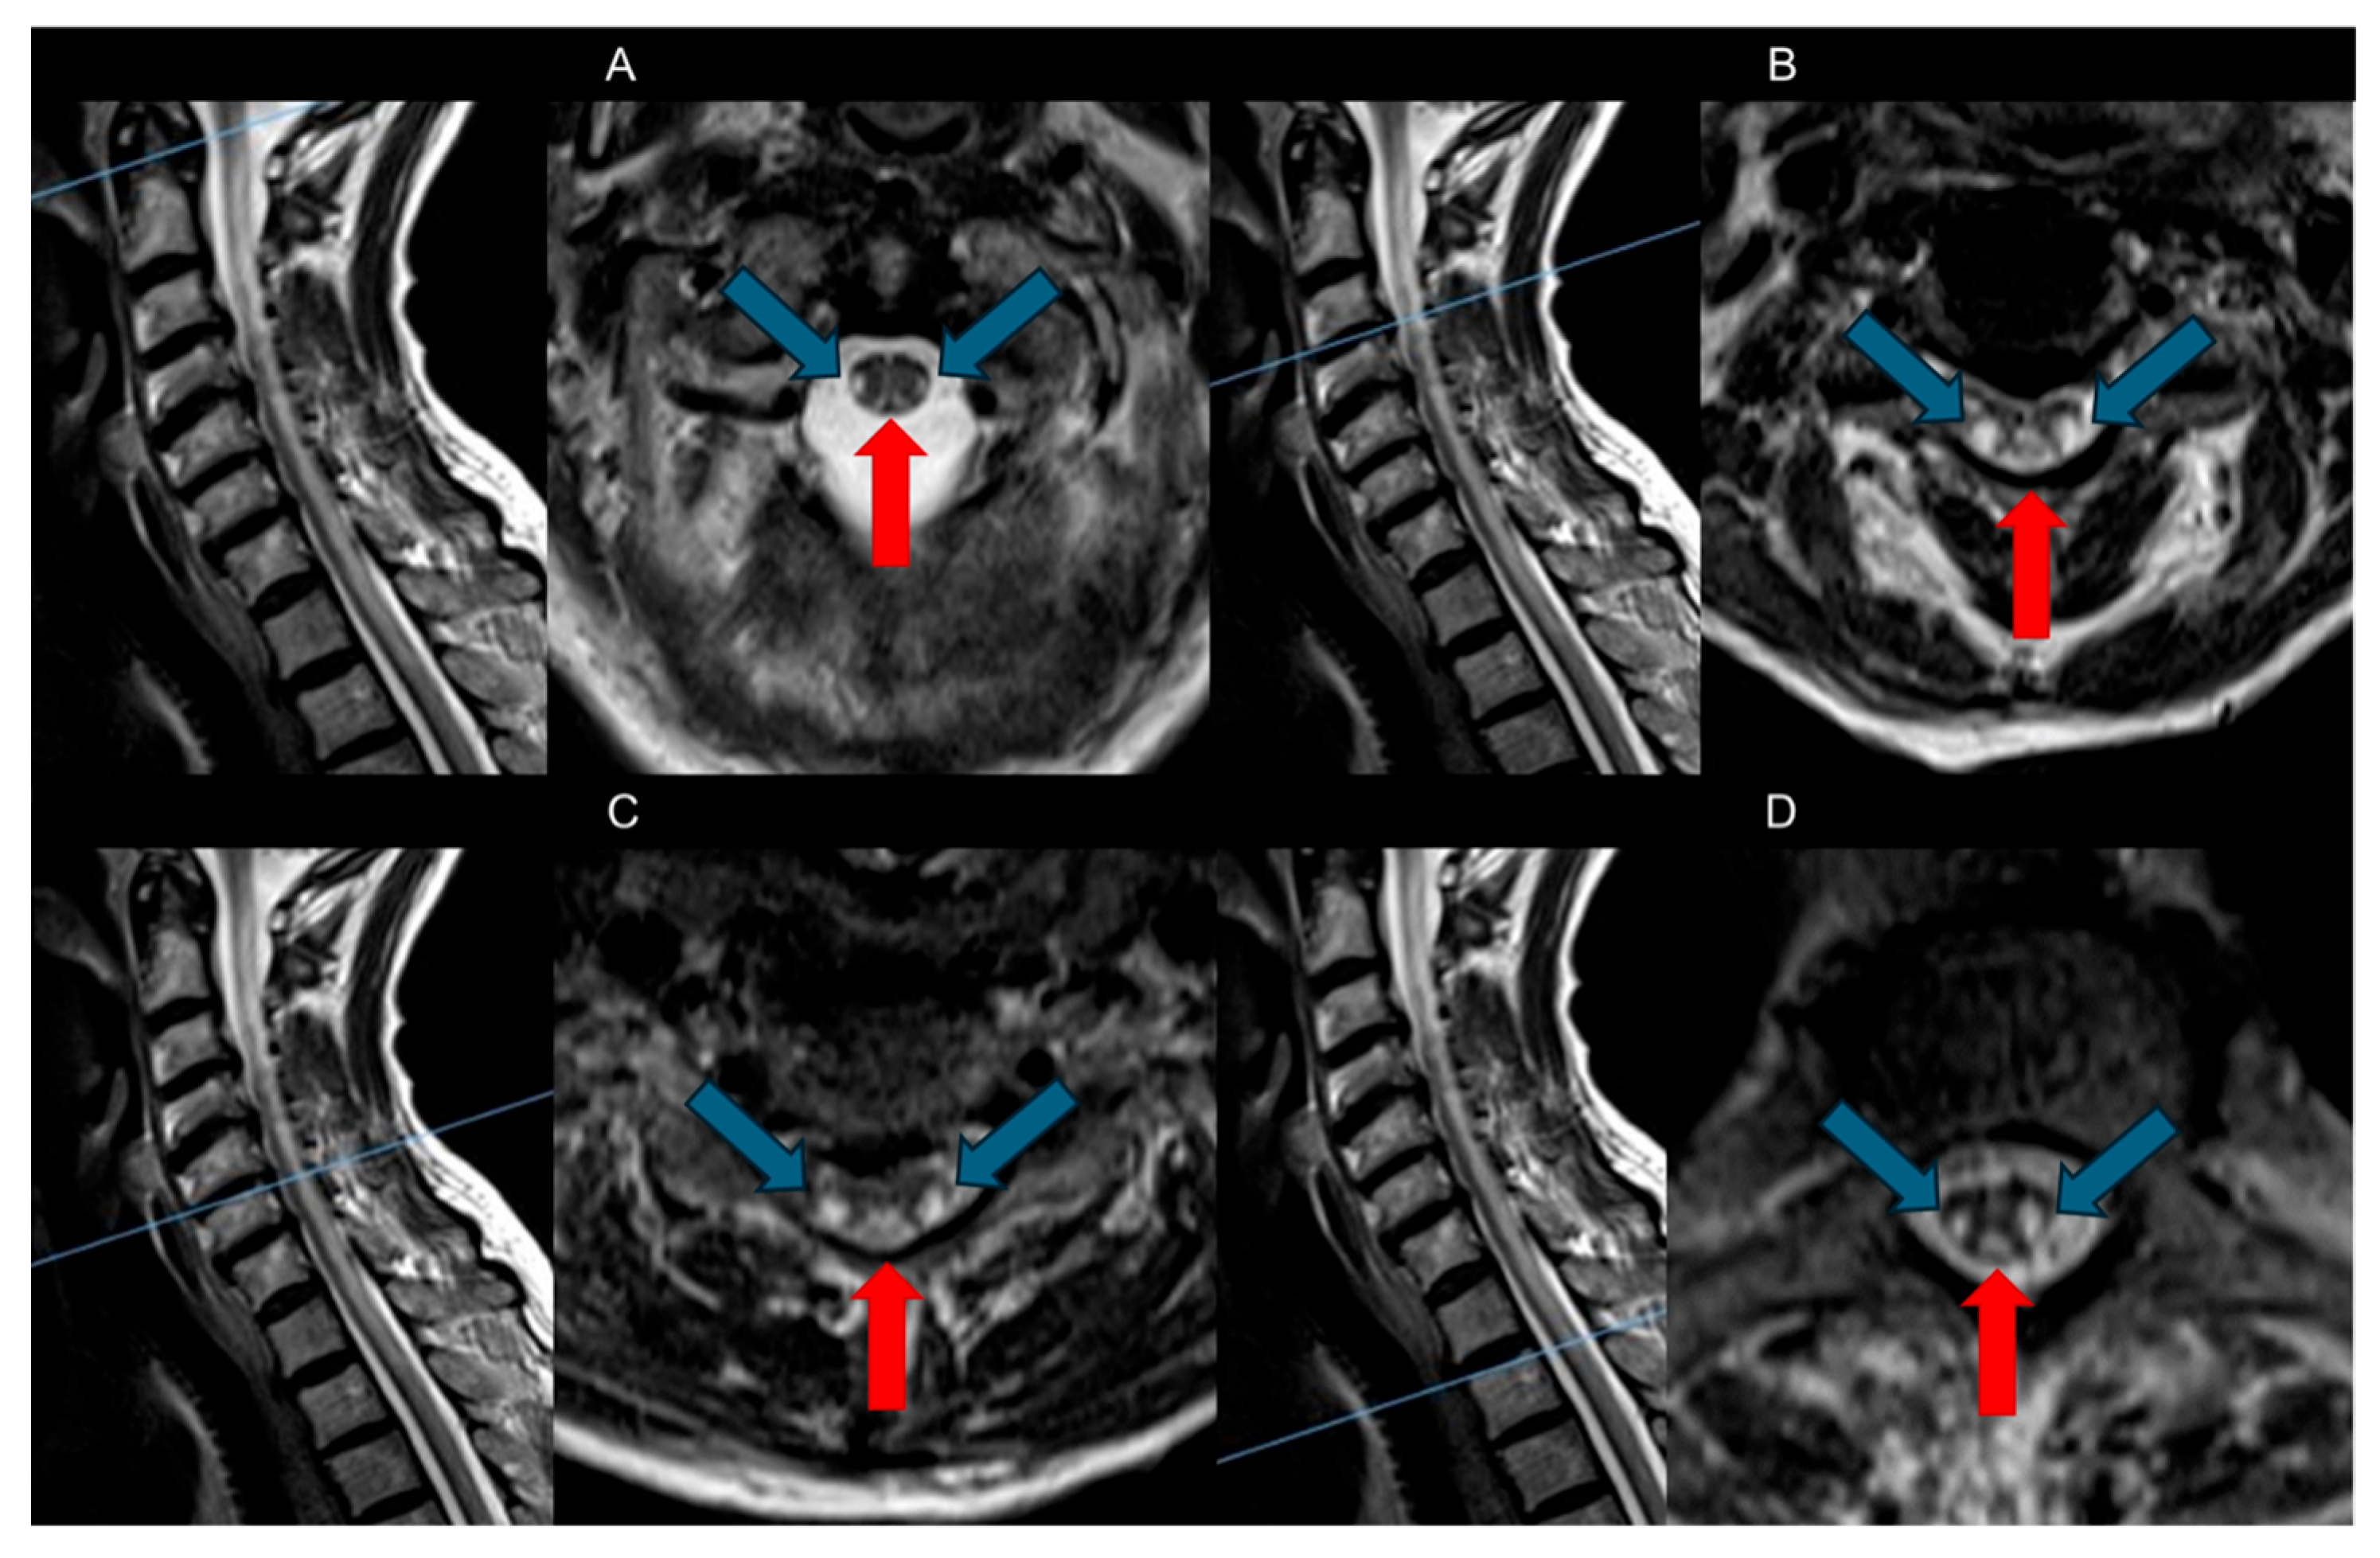

- Dorsal Columns: The most characteristic feature observed in SCD is symmetrical bilateral high T2-weighted signal intensities within the dorsal columns of the spinal cord, often referred to as the “Inverted V” sign or “Inverted rabbit ears” sign. This radiological hallmark typically initiates in the upper thoracic region and may show either ascending or descending progression [8,26].

| Dorsal Columns | Bilateral symmetric high signals lesions (inverted “V” sign) in T2-weighted axial sequences |